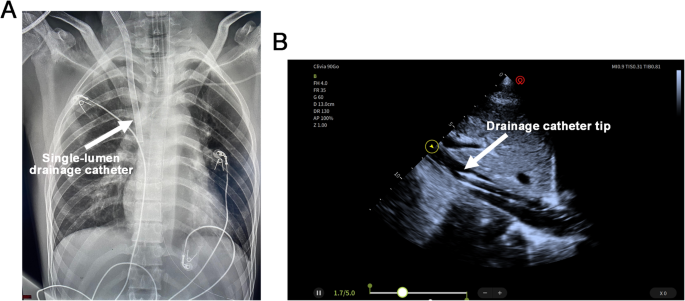

Ultrasound-guided percutaneous cannulation was performed, including placement of a 22-French right IJV drainage catheter and a 19-French femoral artery return catheter. The tip of the drainage catheter was positioned above the hepatic vein confluence within the IVC. Real-time ultrasound guidance was used during insertion, and final catheter positioning was confirmed by chest X-ray and bedside echocardiography (Fig. 2, Supplementary Video 3). The initial ECMO flow was set at 3 L/m²/min. During VA-ECMO support, anticoagulation with unfractionated heparin was administered to maintain APTT between 50 and 60 s, while norepinephrine was continuously infused to maintain mean arterial pressure above 65 mmHg.

The position of the venoarterial extracorporeal membrane oxygenation (VA-ECMO) drainage cannula is confirmed by chest X-ray (A) and transthoracic echocardiography (TTE) (B).